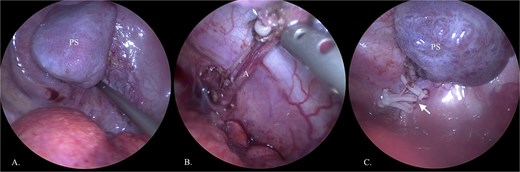

The 2140 g neonate (Apgar 4/5) was shifted to intensive care for respiratory distress, heart failure, and pulmonary hypertension. Patient was discharged after 3 weeks being stable. At 6 months of age, PS was electively removed by thoracoscopy, confirming its torsion (Fig. 2). Recovery was uncomplicated, and the child remains healthy at 2 years of age. Genetic evaluation revealed isolated PS without associated anomalies.

Thoracoscopic removal of PS. (A) Visualized PS in the thoracic cavity. (B) Displayed feeding artery (A) of lung sequestration. (C) Feeding artery is clamped with clips (arrow).